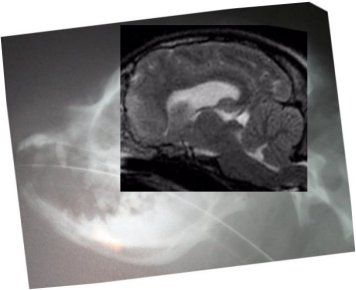

Below are more side skull x-rays of dogs who have also been MRId.

Their diagnosis will be listed below the comps. The idea is to

see if any differences in skull shape could be ascertained from

a simple skull x-ray. Next to it the MRI was fit into the skull

x-ray, just to see where everything fits in. Below is the

result. So far there appears to be a considerable difference in

the shape of the back of the skull between the dogs with SM and

without!

Dog above has moderate to severe malformation and SM with

symptoms